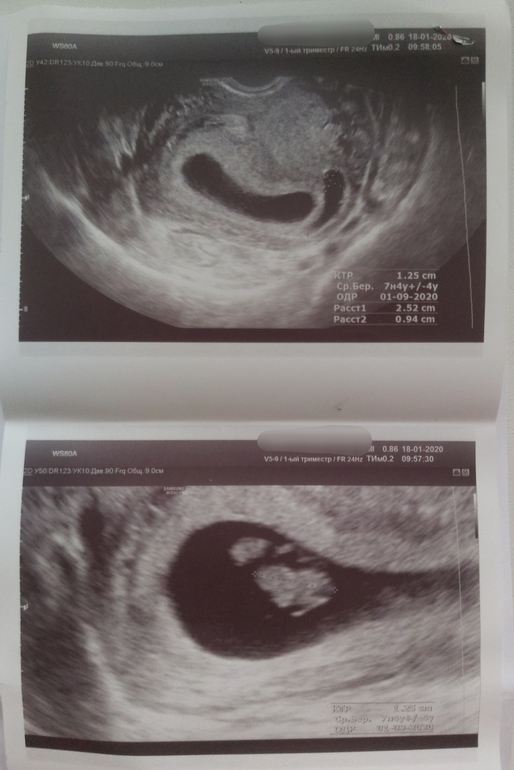

Вчера была на УЗИ. Поначалу все шло хорошо, показали ребеночка, услышала его сердечко 😍💗 166 уд/мин. Показали его мозг)) КТР 12,5мм)) срок по УЗИ 7 нед 4 дн, по месячным 7 нед 6 дн. Потом показали отслойку, 25 * 9 мм...